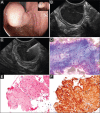

Endoscopic ultrasound (EUS)-guided fine-needle aspiration of a gastric subepithelial tumor. (A) Endoscopic image of an incidental medium-sized subepithelial lesion (SEL) arising from the gastric cardia. (B) EUS reveals a 2 cm, hypoechoic, homogeneous, lobulated SEL with distinct margins, arising from the 4th EUS layer (M. propria, arrow heads). Leiomyoma is suspected. (C) EUS fine needle aspiration using a 22G aspiration needle. (D) Smear cytology (May-Grünwald-Giemsa, x200) and (E) Histology of core particles (Hematoxylin-Eosin, x200) show fascicles of spindle-shaped tumor cells, suggestive of a mesenchymal tumor. (F) Immunohistochemistry (Desmin, x 200: strongly positive; CD117: negative, not shown here) confirms benign leiomyoma. Surgery is not necessary (Photomicrographs D-F by courtesy of Dr. Stephan Wagner, Königs Wusterhausen, Germany)